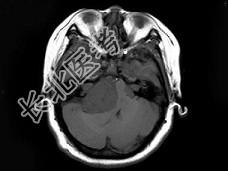

- 单项选择题女,22岁, 胸背部及头皮下多发红色丘疹状突起,伴头痛, 听力下降半年,行头颅MRI平扫及增强扫描如图, 最可能的诊断为 ( )

D、神经纤维瘤病NF-Ⅱ型